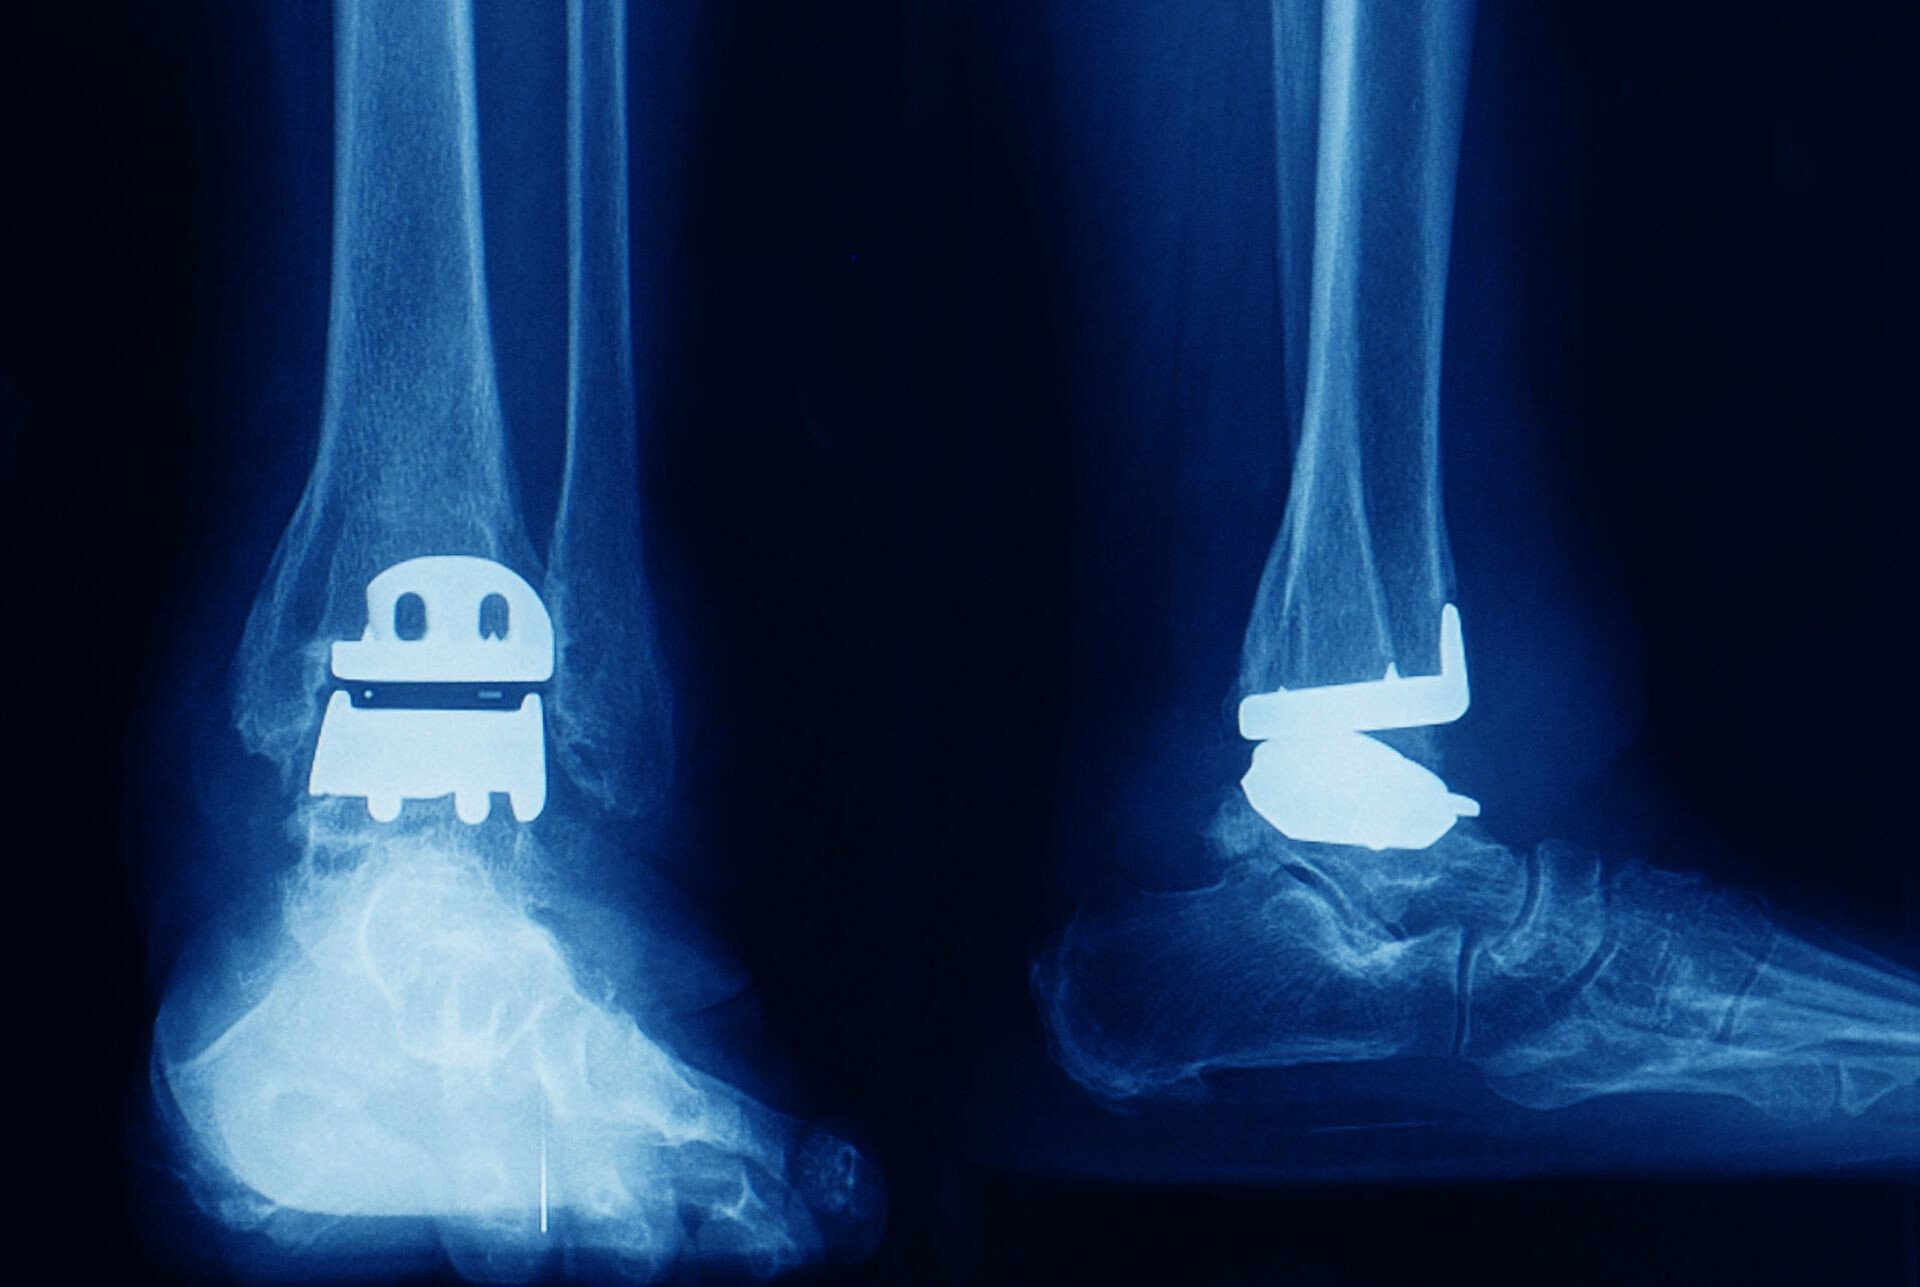

Statistica medicală evidențiază diversitatea nevoilor pacienților, cele mai frecvente intervenții fiind cele la nivelul șoldului și genunchiului. În total, celor 340 de pacienți le-au fost implantate 359 de endoproteze, acoperind o paletă largă de necesități chirurgicale.

„Cele mai multe au fost endoprotezele totale de şold respectiv 146 din care 72 au fost endoproteze totale de şold cimentate și 74 necimentate. Au mai fost implantate 122 proteze totale genunchi cu stabilizare posterioara, 9 endoproteze Moore, 1 endoproteză totală genunchi necimentată revizie, 1 endoproteză totală umăr, 5 pacienti cu elemente de ranforsare cotil şi 75 endoproteze din categoria «alte endoproteze»”, au transmis reprezentanții CAS Olt.